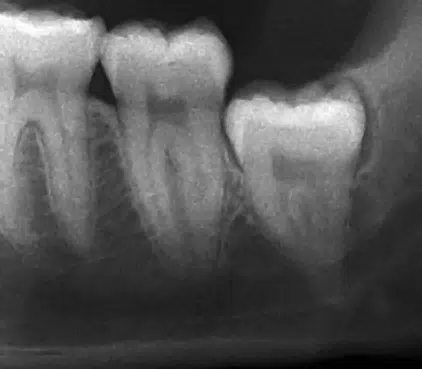

How Dentists Assess Wisdom Tooth Problems

Most dentists will use x-rays to determine how your wisdom teeth are developing. If it looks like they will have room to move in without impacting other teeth or entering your gumline at a strange angle, your dentist might move forward with a cautious wait-and-see approach. If the teeth come in normally and cause no issues, you might simply be lucky enough to have your wisdom teeth with no complications.